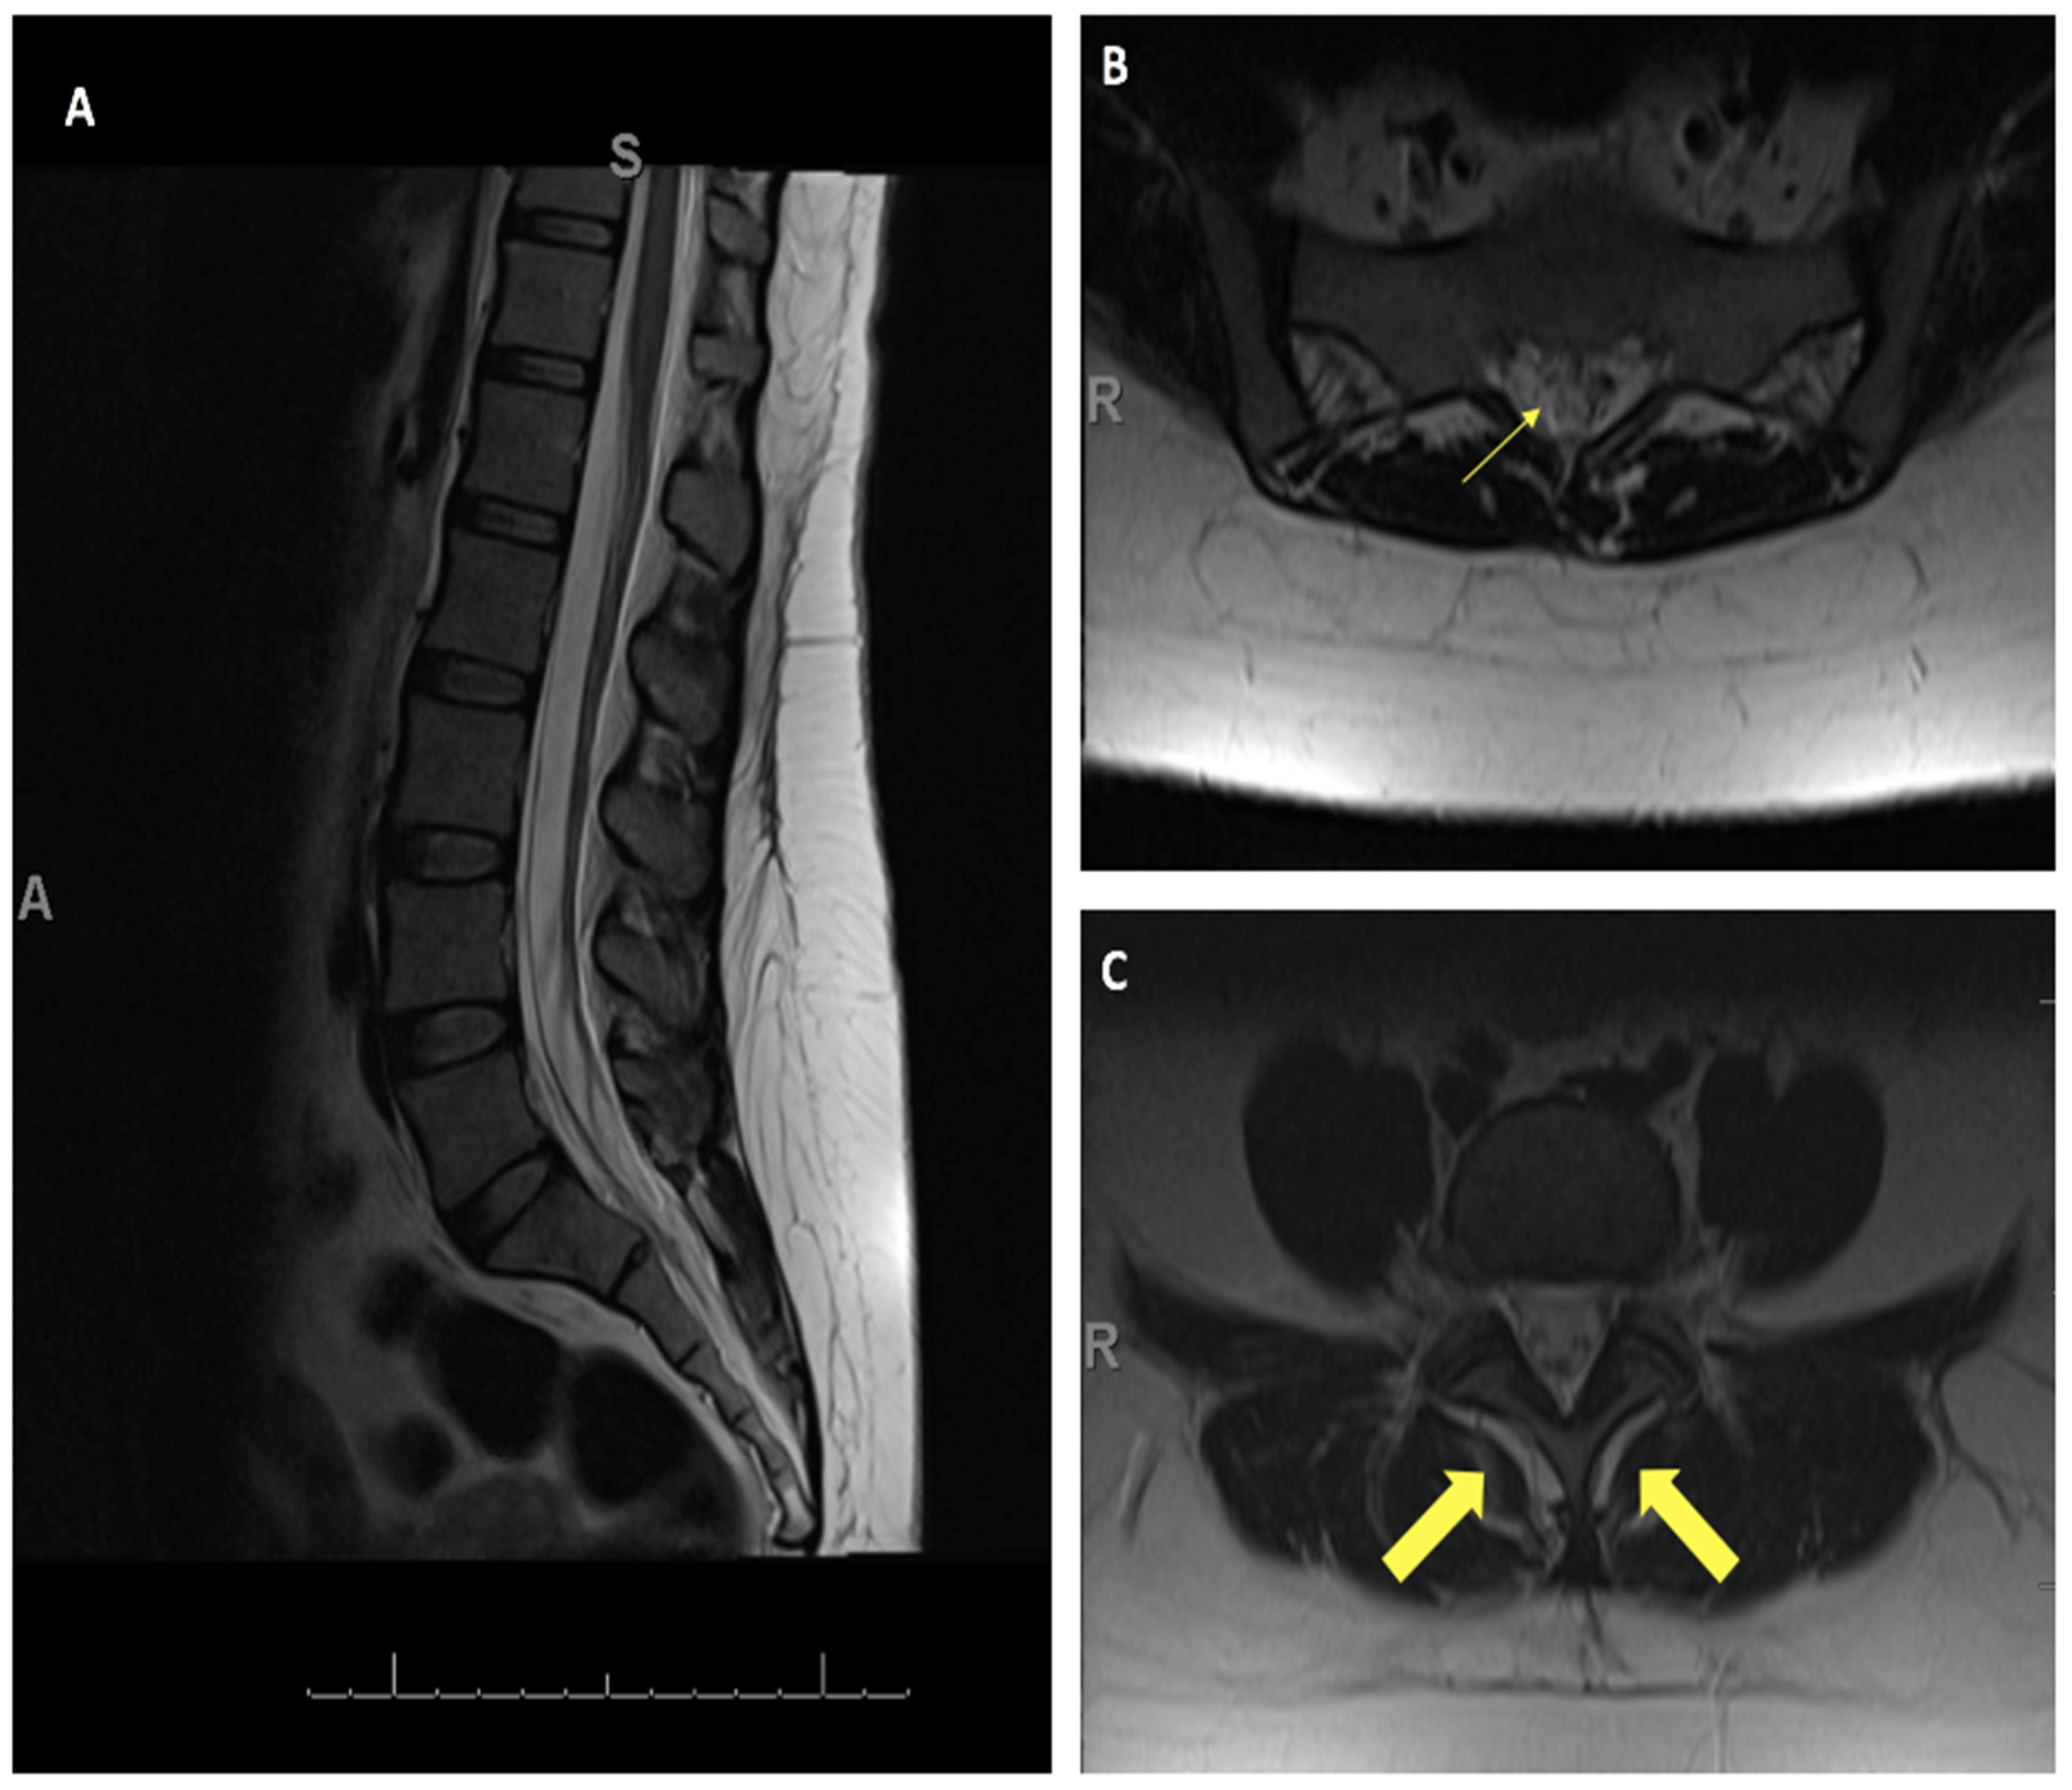

4. Illustrative Case

4.1. Patient Presentation